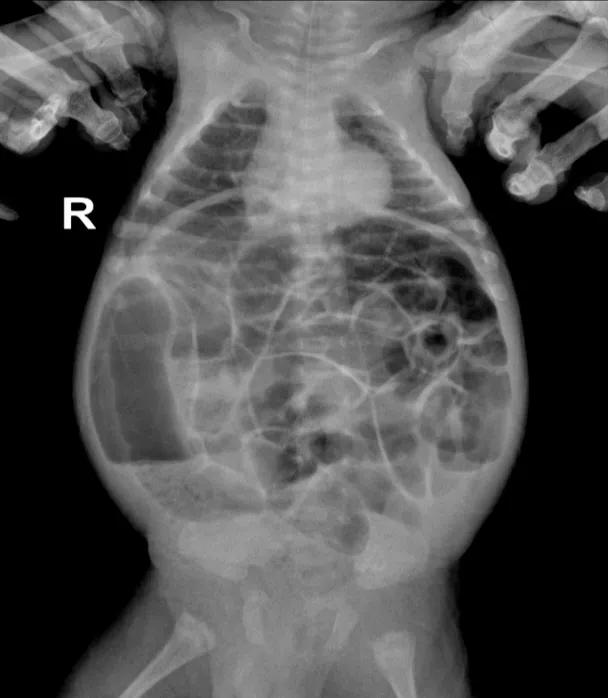

“患儿腹胀特别严重,腹部皮肤发亮,能够看到腹壁下的静脉血管纹路。”张磊介绍,他们立即进行胸腹部立位片检查,通过X线片看到,患儿腹部全是胀气,肠管可见气液平面,确诊为肠梗阻。